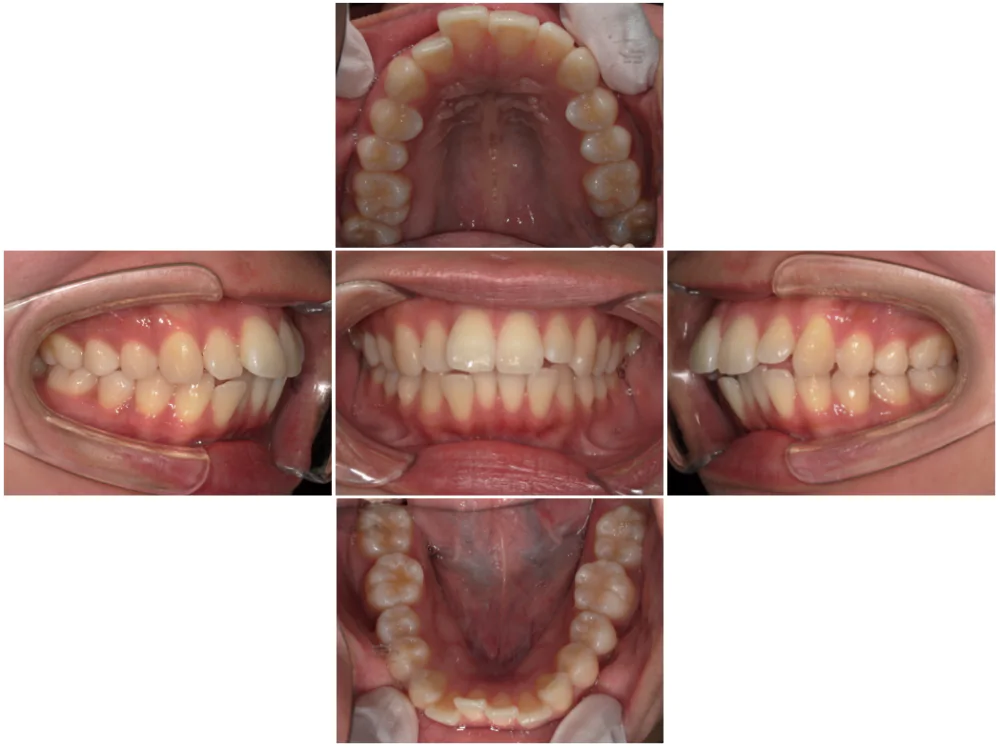

症例5

| 来院時の主訴 | 全体的なガタガタ |

| 医院での対応や適用装置 | 上顎の小臼歯抜歯、ワイヤー矯正にて主訴で |

| 通院期間 | 1年2ヶ月 |

| 通院回数 | 14回 |

| 治療費用総額 | 720,500円(学生割引適応) |

| リスクと副作用 | 矯正治療による歯の移動に伴う痛み、歯根吸収、虫歯 |